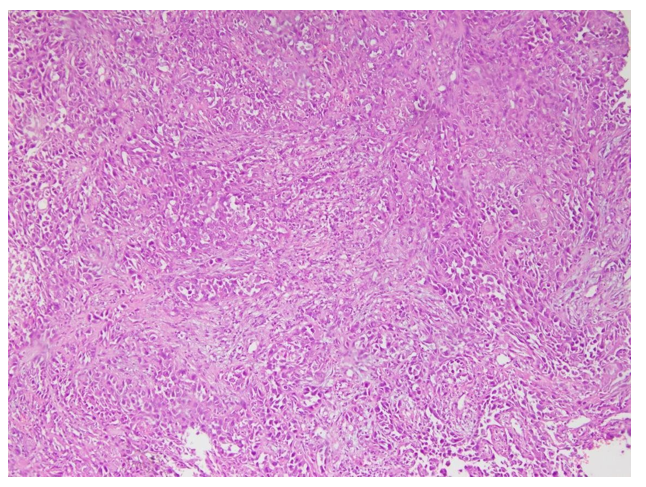

Figure 7: (Case no 51): Photomicrograph of Poorly Differentiated OSCC (Stage T3)

Figure 8: (Case no 51): Photomicrograph of Poorly Differentiated OSCC (Stage T3) with High Cytoplasmic Expression of Vimentin